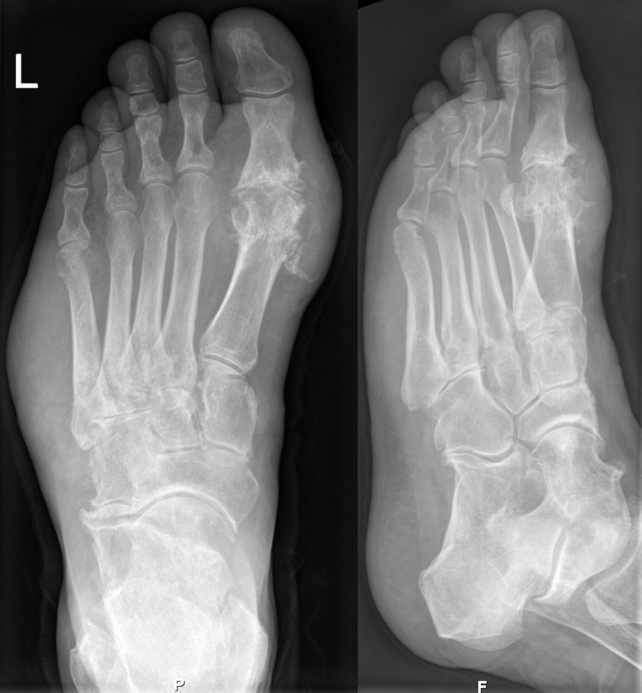

Gout on X-rays of a left foot in the metatarsal-phalangeal joint of the big toe. (Hellerhoff/CC BY-SA 3.0/Wikimedia Commons)

Gout takes hold when there are high levels of uric acid in the blood, which then form sharp crystal needles in the joints. When the body’s immune system starts to attack those crystals, it leads to significant pain and discomfort.